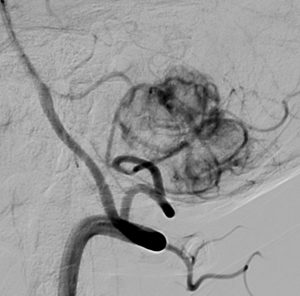

- 椎骨動脈撮影では,著明な腫瘍濃染像(血管がいっぱい)がみられて確定診断が可能です

左小脳にできた小さな のう胞性血管芽腫です。矢印の先にある小さな塊だけが腫瘍で周囲は腫瘍から染み出した液体が溜まっています(のう胞といいます)。右側は血管撮影とMRIを組み合わせた画像で,腫瘍に動脈が流入しているのが見えます。

真偽のほどは解りませんが頭の中で血液が流れる音がするというのが主訴です。その後に軽度の歩行失調と構語障害が出て発見されました。この程度のものでもAVMと同じように血管雑音を自覚することがあるのかもしれません。画像をよく見ると右の小脳扁桃のもので,延髄はただ圧迫されているだけです。血管芽腫はエリスロポエチンを産生して多血症になることがあるのですが,この患者さんは16.6 MIU/mlで正常値でした。

右のPICAが主たるfeeding arteryです。でもPICAのretromedullary segmentからshort feedersが流入していますから,油断をすると延髄背側障害という厳しい手術合併症を生じる可能性は十分あります。この腫瘍は正中後頭下開頭で全摘出できましたし,神経脱落症状を残していません。難易度は中等度のものです。